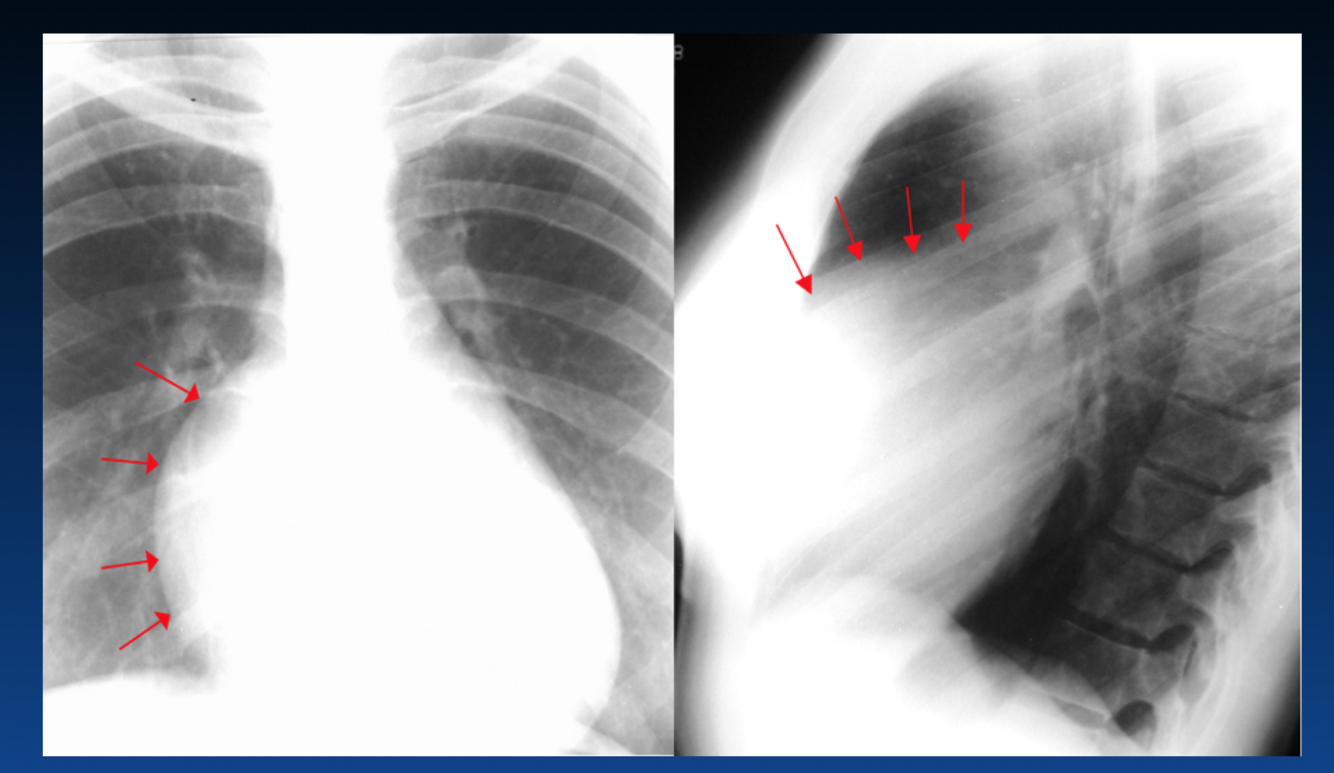

What occurs in this stage of CHF?